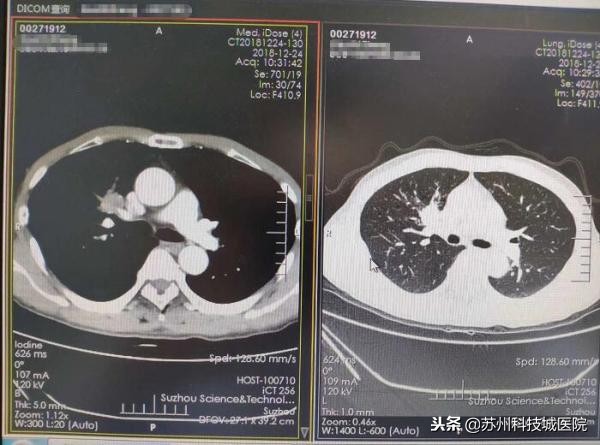

今年59岁的张大伯是一个有着近三十年吸烟史的“老烟枪”,12月下旬,觉得胸口难受的他在儿子的陪同下来到了苏州科技城医院心胸外科,在一系列问诊、CT检查后,心胸外科主任谢骏凭借着丰富的临床经验,明确张大伯得的是右上前段开口鳞癌,且为非常复杂的中央型肺癌中晚期。他第一时间将诊断结果及利害关系告知了张老伯父子,并建议张老伯立即住院,准备手术。张老伯有些犹豫,他希望等病理结果出来再做决定。

要知道,中央型肺癌因为肿瘤位置靠近肺门且隐蔽,周边大血管多,发展到中晚期后,肿瘤细胞将随血流全身扩散,同时还会随着淋巴结转移。如果不及时手术治疗,短时间内可能会出现远处转移,到时候就失去了手术机会。而中晚期的中央型肿瘤,如果不进行手术,患者的3年存活率小于30%,5年存活率更是低于5%。张大伯的手术,可谓刻不容缓!

谢主任介绍,事实上,针对中央型肿瘤患者,因为肿瘤大、手术风险大、难度大等原因,仅有20%左右的患者有条件接受手术治疗。幸运的是,张大伯具备手术条件。考虑到张大伯的肿瘤位置太靠近中央,包绕了肺动脉等重要血管,而且肿瘤已经侵犯到血管和气管,常规的手术入路非常容易损伤肺动脉,引起大出血而导致患者死亡,风险太大。而开胸手术的恢复期大约在一个半月左右,显然太长。经过综合考量,谢主任为张大伯“量身定制”了一个特别的手术路径——单孔手术,先切断支气管,再处理受侵犯的血管,通过微创手术的形式,远离肿瘤进行切除。为了确保术后没有残留一个癌细胞,在术中,谢主任还为张大伯做了冰冻病理,以及系统淋巴清扫。